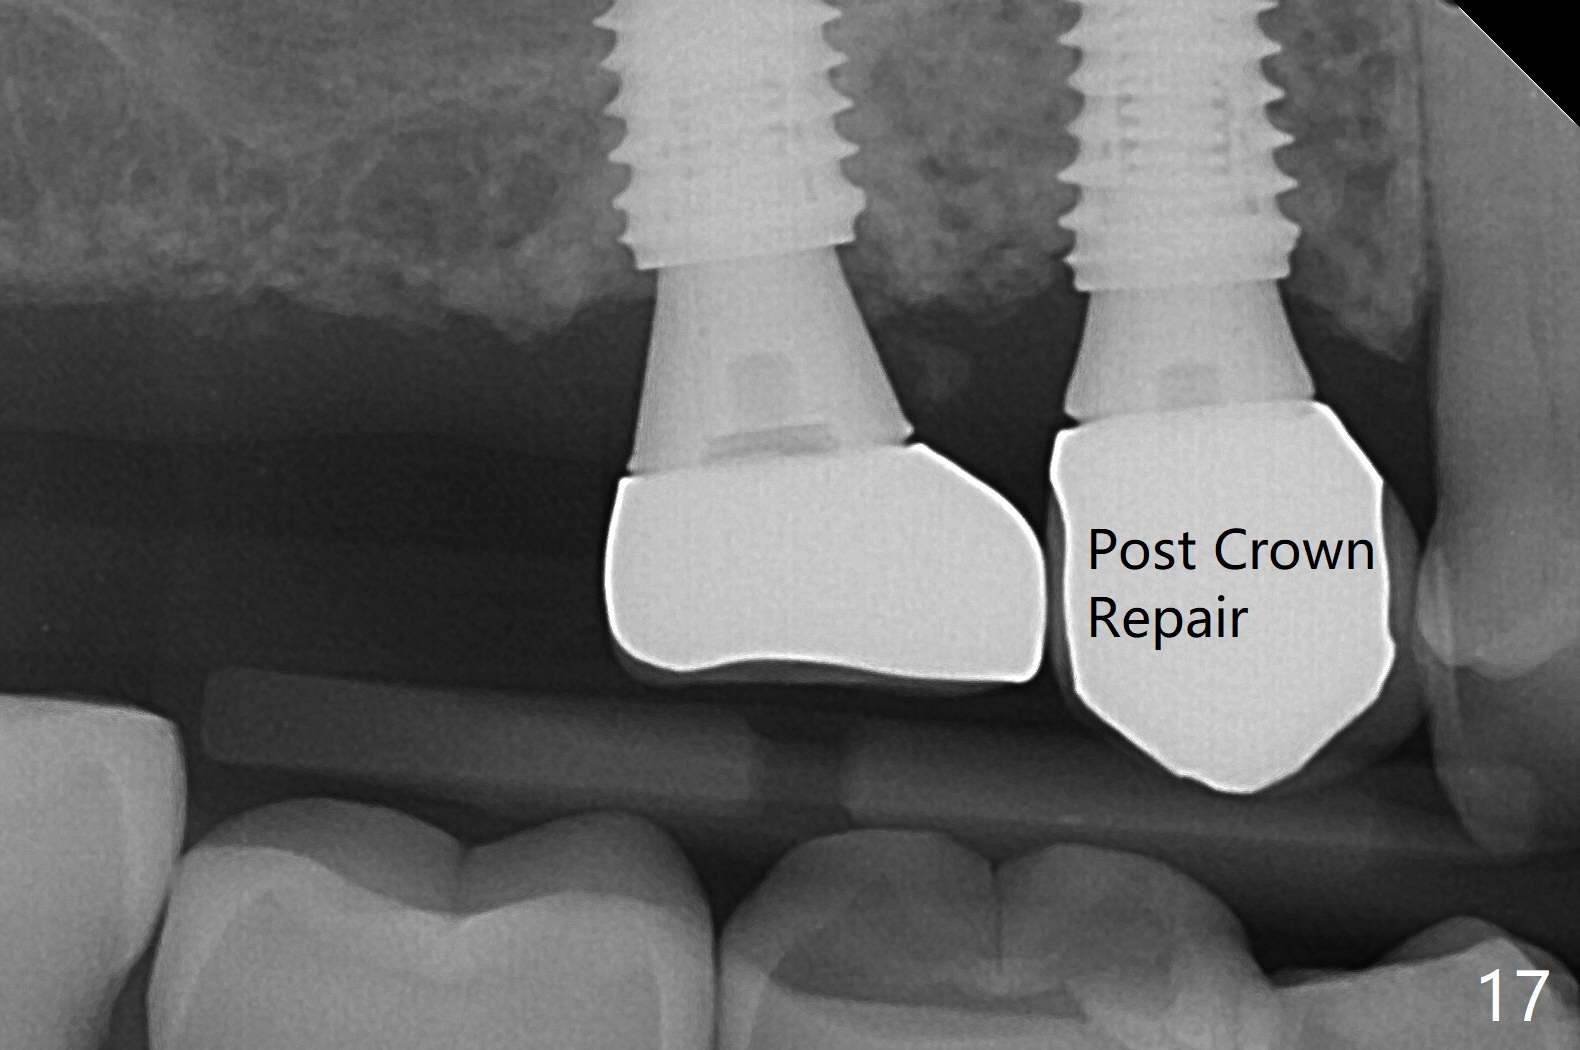

Osteotomy at #3 is performed last (Fig.1,2); as planned, a 4 mm cortical tap is used with guide for sinus lift. Unfortunately the sinus membrane is perforated. Implant placement is aborted. Instead Osteogen plug is inserted into the osteotomy, which is fixed in place by acrylic extending from the provisional at #4. Osteotomy for #3 implant will be attempted with control of the depth in 4 months. The patient has allergy to Amoxicillin (rash). When switching to Clindamycin, she develops diarrhea and loses 10 pounds. There is no abnormality at the site of #3 or 4 nearly 3 months postop (Fig.3). The next surgery will be most likely conducted without antibiotic 4 months postop. Try to draw blood for PRF. Take PA for #12 and 13 for possible impression. Remove the 3 temporary crowns, seat the guide across the arch and use no-stop fixture mounts at #4, and possibly 12 and 13. Follow the original drill sequence (check perforation after each drill, Fig.11) and use DIONavi sinus approach kit. Also load an appropriate stop for the round bur for sinus lift before hand. Mixture allograft with Metronidazole and PRF. In fact everything goes on as smoothly as planned. Osteotomy at #3 is underprep (3.5 mm in diameter drill instead of 4.0). The sinus floor appears to remain to be absent; 3.2 mm round bur is used for lift, alternating with water pumping. Following insertion of 3 pieces of PRF membranes and Vanilla Graft (Fig.4 *), a 4x10 mm dummy implant is placed. After additional bone graft (Fig.5 *), a final 4.5x7.3 mm implant is placed ~10 Ncm. The implant is placed deeper ~ 1 mm, followed by a 5.5x3 mm healing abutment (Fig.6). The implants at #12 and 13 seem to have osteointegrated (Fig.7). Impression is taken for #4, 12 and 13 with limited vertical space (Fig.8,9). An implant at #14 is being considered. There is faint bone graft around the apex of the implant 4 months postop (Fig.10). The implant sustains 25-30 Ncm torque when a 5.2x4(3) mm cemented abutment is placed. A permanent crown is cemented nearly 5 months postop (Fig.11). For the best cosmetic and masticating results, the occlusal surface should have certain degree of morphology, such as the buccal cusps (Fig.12 white curved lines). The abutment at #3 is placed and torqued to 30 Ncm before re-cementation of the repaired crown (increased occlusal surface contact). In fact the abutment at #4 is incompletely seated with a gap (Fig.13 <). The composite at #5 is dislodged while #3 crown is being repaired (*). The abutment at #4 is loose >1 year post cementation. The abutment remains incompletely seated (gap and longer apical space (double arrows)) when the abutment/crown complex rotates lingual mesiobuccal (Fig.14 curved arrow). Further proximal reduction and lingual rotation distobuccal leads to complete seating (Fig.15). It appears that incomplete seating at #13 is associated with hex mismatch (Fig.16, large apical space), which will be fixed next visit. One week later, the crown and abutment of #4 are seated together after crown repair (Fig.17). Since the abutment margin is subgingival, the crown is cemented, removed with abutment for residual cement removal and reseated with the abutment with torque at 30 Ncm. After this, the crown and abutment of #13 is reseated after mesiobuccal surface is trimmed (Fig.18), followed by pick up impression. A few days later, the crown/abutment are inserted together smoothly, the former cemented and the complex unscrewed for residual cement removal and last torqued at 30 Ncm without any X-ray confirmation.